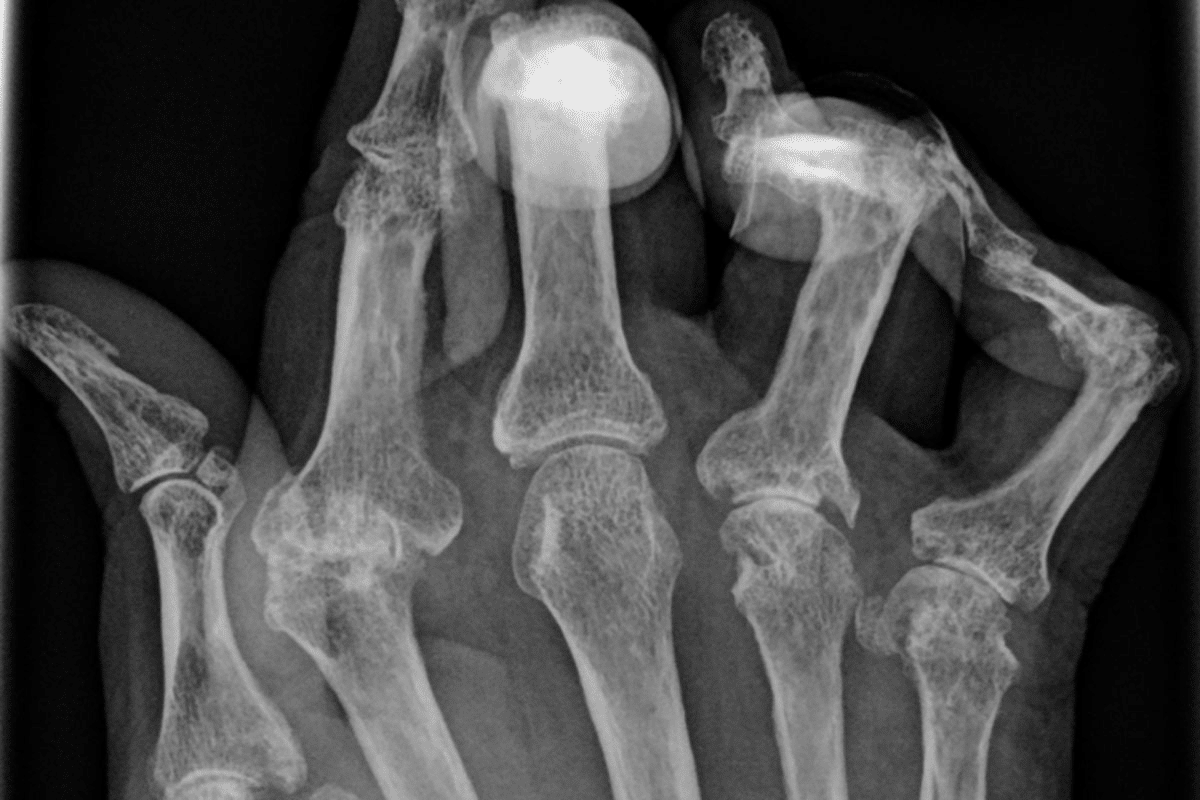

Osteoarthritis Imaging

Osteoarthritis (OA) is the most common arthritis, caused by cartilage breakdown in joints. MRI shows OA well, including cartilage loss and bone spurs. This helps us understand how severe OA is and what treatment to use.

X-rays have been used for years to check bones and joints in arthritis patients. But they don’t show soft tissues well. MRI, on the other hand, is great at showing soft tissues like cartilage and ligaments. This is important because soft tissue changes often happen before bone damage.

MRI can spot inflammation and cartilage wear early. This early detection helps doctors act fast, which can slow down the disease.